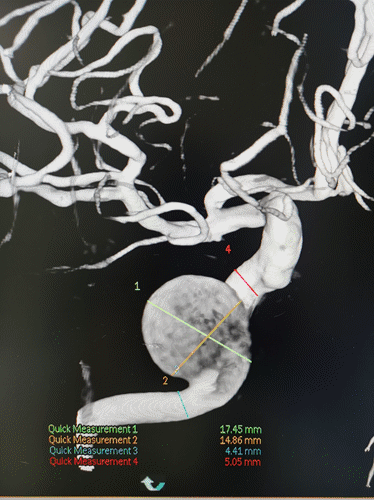

右颈内动脉海绵窦段起始部类圆形瘤样扩张,最大约19mm╳14mm,瘤颈约14mm,基底动脉中段重度狭窄。

图4右颈内动脉海绵窦段起始部类圆形瘤样扩张,最大约19mm╳14mm,瘤颈约14mm,瘤内射流明显,载瘤动脉远端5mm,近端4.5mm。